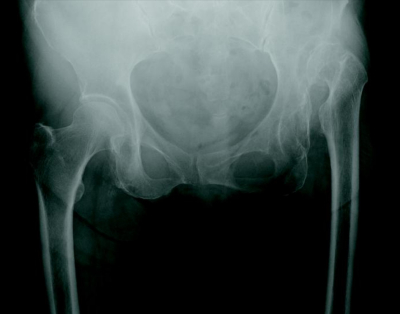

78 歳の女性。左股関節痛を主訴に来院した。10 年前に誘因なく左股関節痛が出現したがそのままにしていた。最近になり痛みが増悪したという。股関節部エックス線写真を別に示す。

治療法として適切でないのはどれか。

a. 杖使用

b. 筋力訓練

c. 徒手整復

d. NSAID 投与

e. 人工股関節全置換術